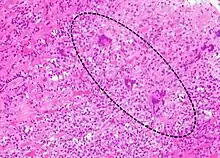

Endomyocardial biopsy specimen with extensive eosinophilic infiltrate involving the endocardium and myocardium (hematoxylin and eosin stain)

The gold standard is the biopsy of the myocardium, in general done in the setting of angiography. A small tissue sample of the endocardium and myocardium is taken and investigated. The cause of the myocarditis can be only identified by a biopsy. Endomyocardial biopsy samples are assessed for histopathology (how the tissue looks like under the microscope): myocardial interstitium may show abundant edema and inflammatory infiltrate, rich in lymphocytes and macrophages. Focal destruction of myocytes explains the myocardial pump failure.[10] In addition samples may be assessed with immunohistochemistry to determine which types of immune cells are involved in the reaction and how they are distributed. Furthermore, PCR and/or RT-PCR may be performed to identify particular viruses. Finally, further diagnostic methods like microRNA assays and gene-expression profile may be performed.